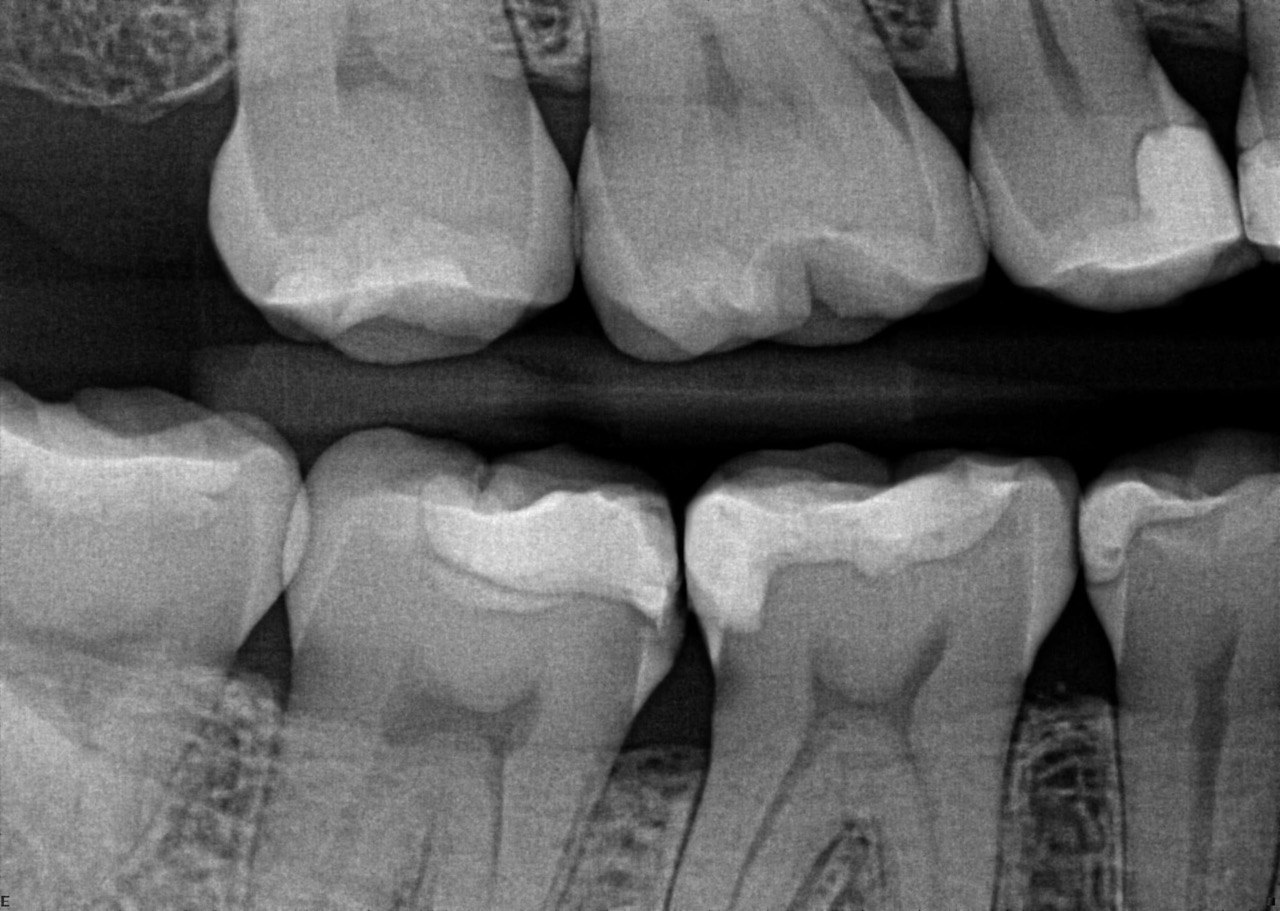

8. What condition can be seen in the distal surface of the tooth # 2.4?

9. What condition can be seen in distal surface of the tooth # 2.6?

10. What condition can be seen on the teeth # 1.5 and 1.4?

11. What is the radiolucency on the teeth # 1.1, 1.2, 1.3?

12. What is the condition showed by the arrow?

13. What condition can be seen on the teeth # 4.4 and 4.5?

14. What condition can be seen on the root surface of tooth # 1.1.?

15. What condition can be seen on the buccal surface of the tooth # 4.2?